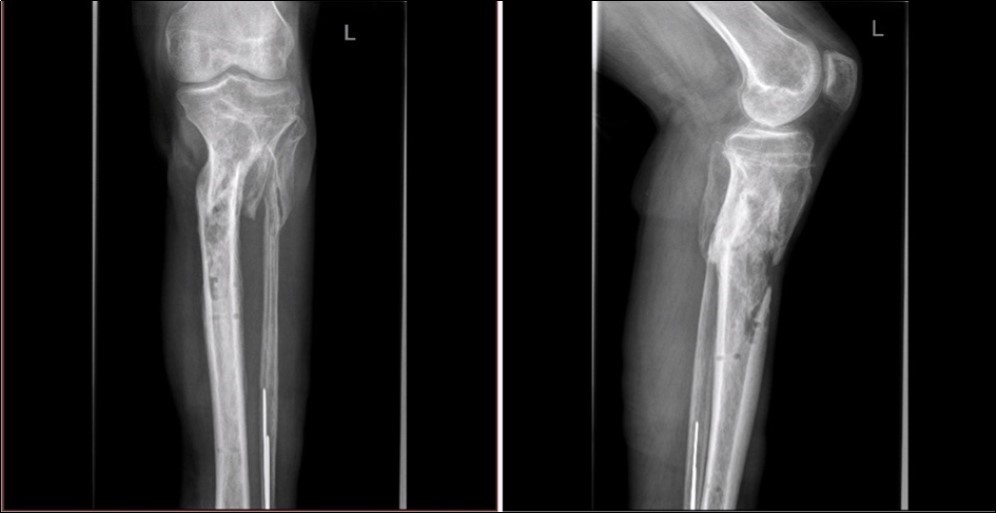

Figure 33. X-ray documentation of the whole treatment of tibia fracture. External fixation was used throughout the treatment until bone was healed. From 9.October 2015 to 2.February 2017